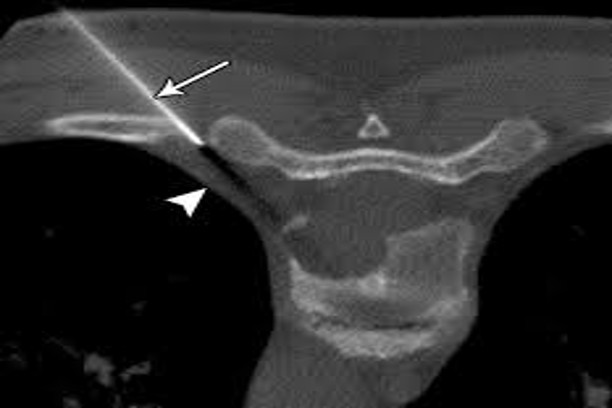

Reduction and fixation of jaw bone fractures

Stabilization and healing of facial bone injuries.